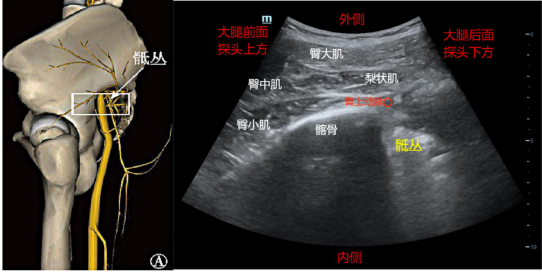

(一)后路骶丛:短轴入路法

超声准备:低频探头,深度6-10cm。体位:侧卧位。

解剖关键点:髂后上棘、坐骨结节,臀大肌、梨状肌、坐骨大孔。

扫查方法:探头垂直放置在髂后上棘与坐骨结节连线的中上三分之一交界处,向下滑动和倾斜,当骨皮质连续中断时,即可见到梨状肌和梨状肌下方的骶丛。此时探头以相对人体的内侧向头侧方向旋转60°左右,可以获得坐骨神经长轴的高回声的声像图。

穿刺方法:平面内法,一般选择从外侧向内侧进针,在梨状肌深面、骶丛外侧和浅面注射局麻药10ml。然后调整穿刺针,在髂骨内侧缘与骶丛的间隙,向深面进针再注射10ml局麻药,总量为20ml。穿刺过程要避免穿通骶丛神经,避开臀大肌和梨状肌之间的臀上动脉、骶丛内侧和骶丛深面的臀下动脉和阴部内动脉等血管。

药物用量:0.375%-0.5%罗哌卡因15-20ml。